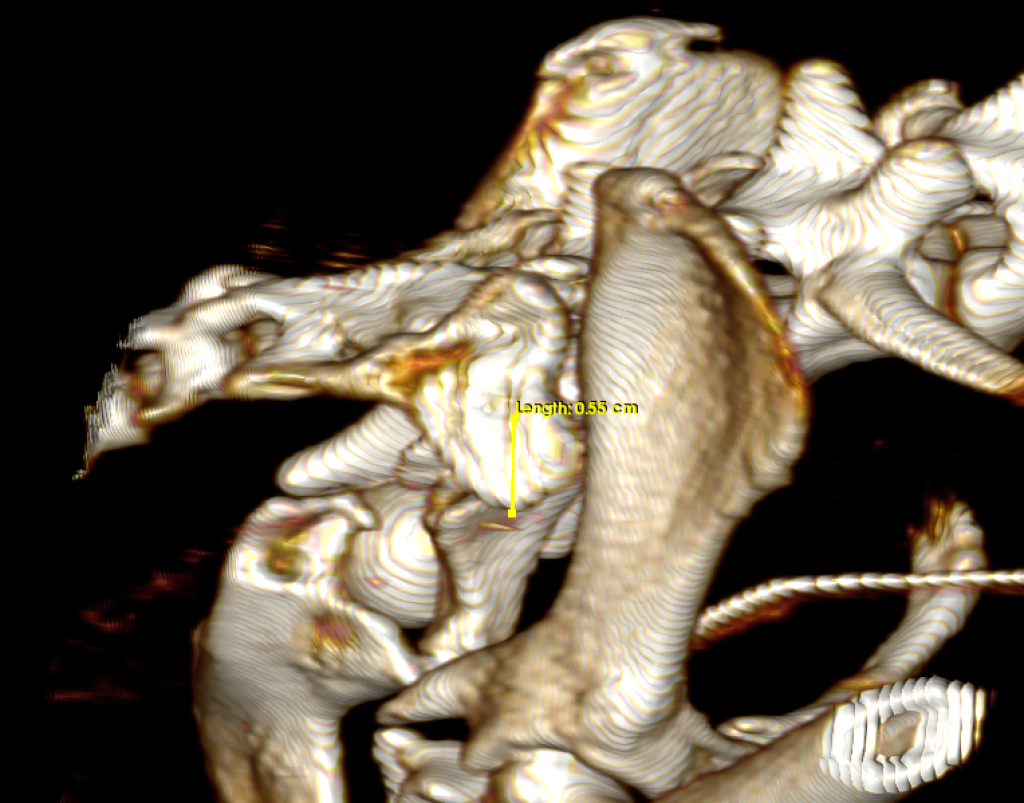

Para obtener un diagnóstico definido, procedimos a realizar un protocolo diagnóstico completo, que incluyó un estudio radiológico y tomográfico de la pelvis. Gracias a las imágenes pudimos confirmar el diagnóstico, una fractura múltiple de pelvis con luxación sacroiliaca derecha, y luxación coxofemoral izquierda a consecuencia de una fractura conminuta del acetábulo.

Para poder definir con mas precisión todos los daños y establecer el mejor plan quirúrgico realizamos una tomografía computarizada (TAC) de la pelvis.

La estabilización quirúrgica de la pelvis no resultó sencilla. En primer lugar se realizó un abordaje lateral al ilion y acetábulo izquierdo, a través de una osteotomía de trocánter mayor. Al comprobar la imposibilidad de reducción de los fragmentos que comprometían el acetábulo, se tomó la determinación de realizar una exéresis de la cabeza y cuello femoral. A continuación se estabilizó la fractura de la hemipelvis izquierda mediante una placa de bloqueo y titanio de 1´5 mm. La osteotomía del trocánter mayor se redujo y estabilizó por su lado con una banda de tensión.

En segundo lugar se realizó un abordaje dorsal a la articulación sacroiliaca derecha, que se encontraba luxada. Se redujo y estabilizó con dos tornillos para garantizar la fijación adecuada.